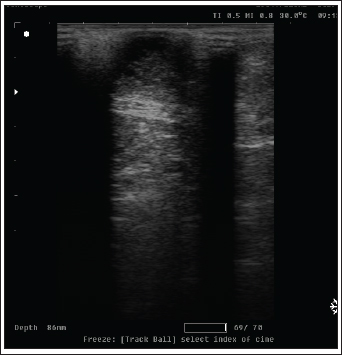

On ultrasound images, mammary gland tissue showed higher echogenicity than normal tissue. The FMH lesions were well-defined, slightly hyperechoic, lobulated masses containing multiple small anechoic clefts within the mammary parenchyma.

The intraductal pattern is dominant, with anechoic areas corresponding to clefts of different shapes within the mammary gland parenchyma. The presence of clefts in mammary fibroepithelial lesions provided a more heterogeneous appearance to the ultrasound images (Fig. 4). In the solid lesions, the ultrasound pattern is more homogeneous (Fig. 5).

Fig. 5. Ultrasonographic image of a solid pattern lesion.

Radiology was of little interest in cases of FMH, as lateral abdominal surveys only reveal the enlargement of the mammary glands with an intact body wall (Burstyn, 2010). In comparison, ultrasonography provides more valuable information about the assessment of lesion pattern and echogenicity. Similar findings have been reported (Payan, 2013). In the present study, medical treatment was administered to 25 cats using cabergoline drug administration (5 µg/kg once daily PO), which proved effective in the majority of treated cats, leading to substantial regression of mammary size within three to 6 weeks, as previously reported (Giménez et al., 2010; Akkuş and Yaprakcı, 2024).